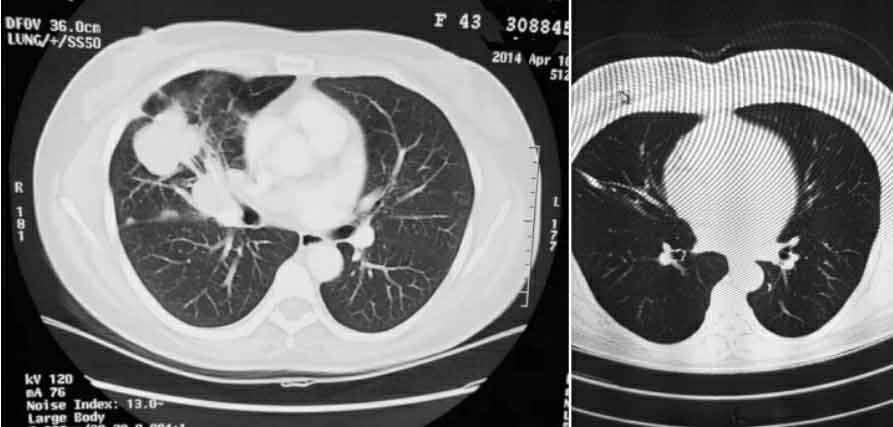

是的,她来得确实太晚了。尽管我不搞肿瘤专业,但也可以从她的CT片上粗略地看出她右肺中叶的肿瘤已经侵犯到了上叶,肺门淋巴结肿大,胸膜上有结节,这些结节大概率是转移来的。

2014年,她43岁,她只求再活上个一年半左右就行。但真的太晚了,我基本不抱希望。从她的CT片子上看,她的癌症已经进展到了IV期[医生通常根据患者肿瘤的大小和邻近组织受累范围、淋巴结受累情况、远处转移情况对肿瘤进行分期,这种分期方式称为TNM分期,TNM分期有Ⅰ、Ⅱ、Ⅲ、Ⅳ四期,分期越高意味着肿瘤进展程度越高,病程越晚,Ⅳ期为最晚期。],而研究数据表明,这一期肺癌患者五年生存率不足10%,平均中位生存期是七个月。换句话说,每一百个像她这样的晚期肺癌患者中,能活过五年的不到十个人,有一半活不过七个月。

患者提供的2014年刚发现肺癌时的胸部CT(左)及经过治疗后的胸部CT(右),刊登已获患者授权

“没想到,靶向药对我的效果特别好,”她说,“我吃了三个月以后,肿瘤明显缩小,治疗前胸膜有转移,吃药后转移也没了,而且也没太大副作用。”

“用上新药一个月后肿瘤明显就缩小了,再继续用,肿瘤基本没有了,我肺上完全看不到肿瘤了。